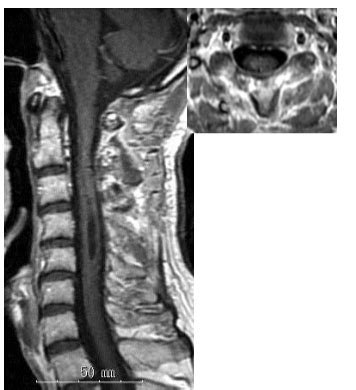

脊髄腫瘍 | 総合東京病院【公式】中野区 練馬区 24時間救急受入

脊髄腫瘍 | 総合東京病院【公式】中野区 練馬区 24時間救急受入 from www.tokyo-hospital.com